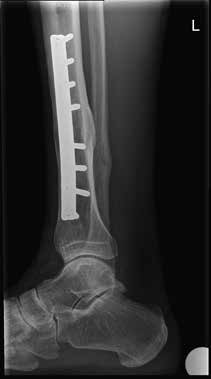

Dem Patienten wurde eine orthopädische Innenschuhorthese als Versorgung vorgeschlagen (Abb. 2). Um diese zu testen, wurde dem Patienten ein abnehmbares Soft-Cast-Stiefelchen (Abb. 3 und 4) mitgegeben. Dieses konnte sofort angefertigt werden und zeigte unmittelbar den gewünschten Erfolg, sodass die vorgeschlagene Versorgung nach kurzer Zeit ausgeführt werden konnte (Abb. 5).